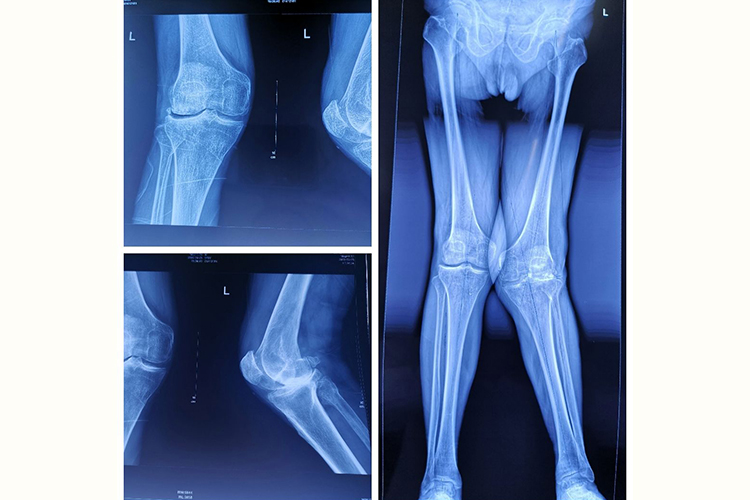

膝盖内扣的医学专业名词为膝外翻,是一种下肢向内弯曲畸形。

膝盖内扣患者以两下肢自然伸直或站立时,两膝能相碰,两足内踝分离而不能靠拢为主要表现。在1.5-6岁期间的儿童,存在轻、中度膝外翻为发育性膝外翻,是正常生理现象。严重膝外翻的患儿出现摇摆步态,呈“内八字”步态。

患者站立时,因双膝相碰,常使一侧稍屈而处于另一膝的前方,另一膝则过伸而处于后方。此种姿势也容易引起疲劳,在快步行走或奔跑时,双膝易碰撞而跌倒。